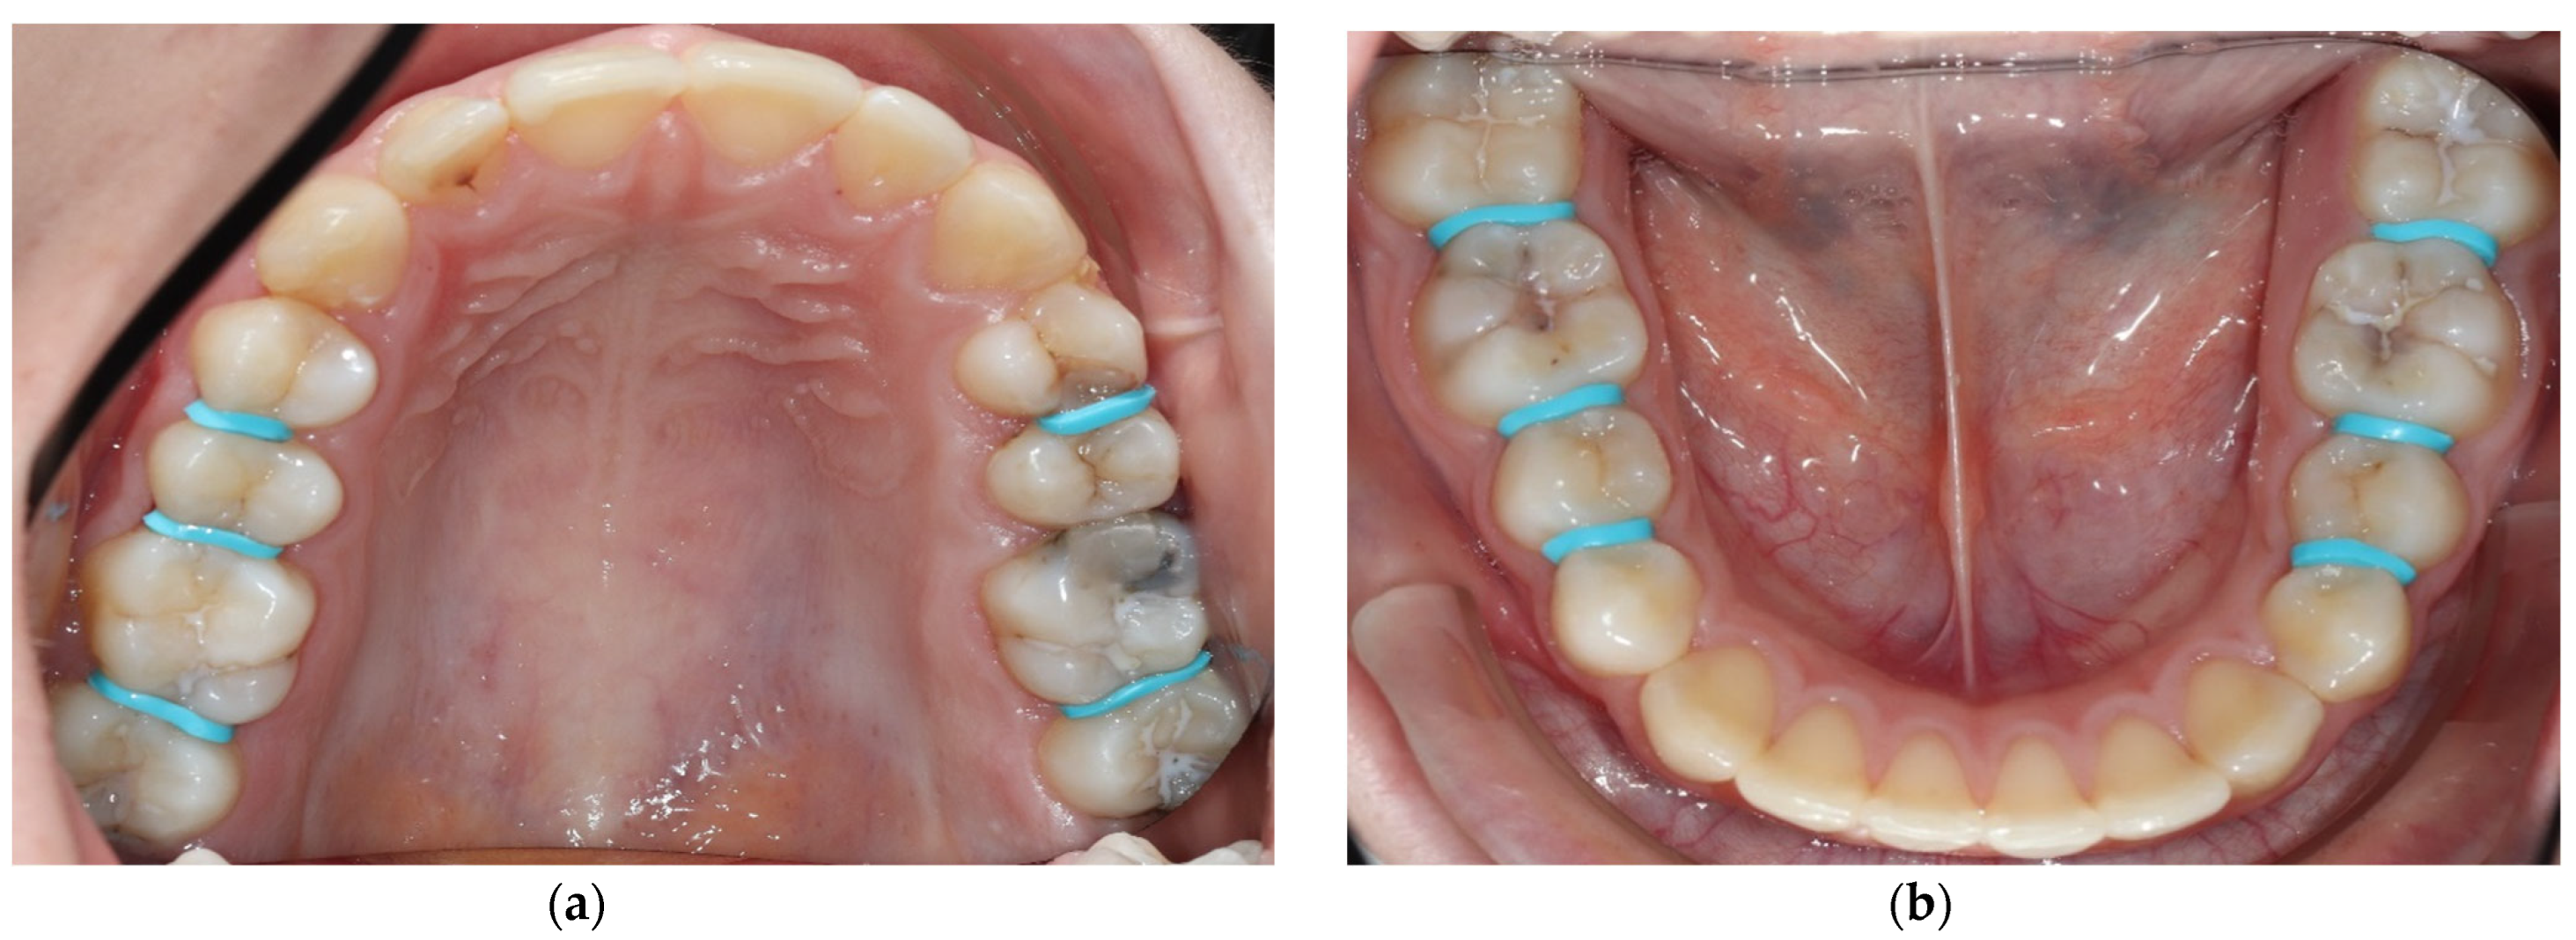

- Tooth separation with orthodontic rubbers: This revealed the absence of cavitation (Figure 3a,b).